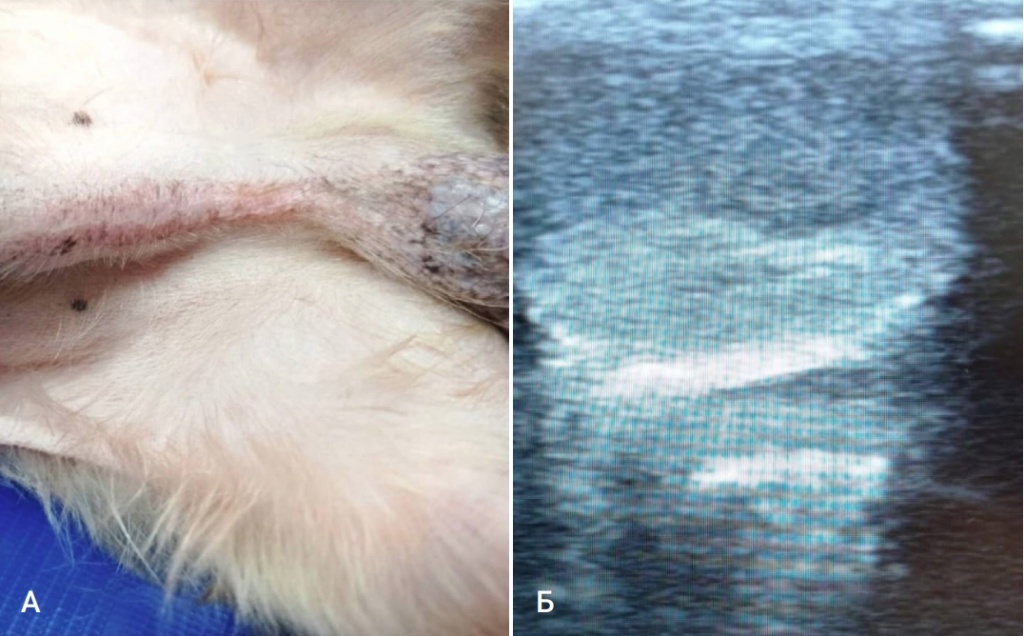

А - линейный препуциальный дерматоз, Б - новообразование семенника на УЗИ

В процессе осмотра животного был выявлен линейный препуциальный дорсальный дерматоз (фото 1A), как известно, данный признак является патогномоничным для кобелей с гиперэстрогенизмом. На осмотре при проведении пальпации патологических изменений семенников выявлено не было.

На ультразвуковом исследовании половой системы кобеля было выявлено новообразование семенника (фото 1Б).